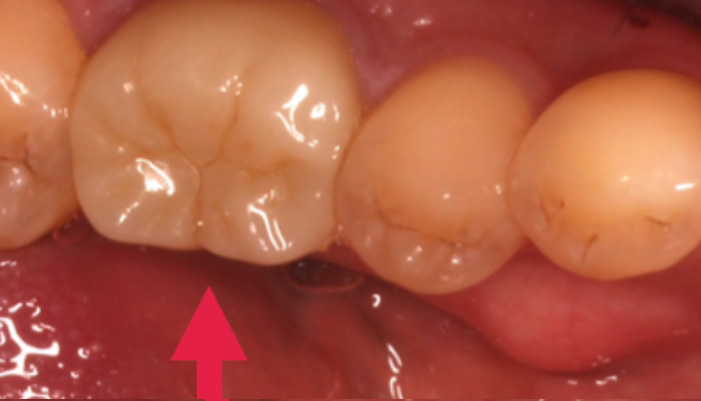

症例2

治療前

治療後

治療の経緯

患者様は「破折した奥歯にインプラントをしたい」とのご希望で来院されました。診査の結果、歯根破折に加えて骨の吸収が進んでおり、そのままではインプラント治療が難しい状態でした。そこで、骨造成を併用してインプラントを埋入できる環境を整えるとともに、歯肉の形態も調整し、機能面と清掃性に配慮した治療を行いました。

同じ症状で悩んでいる方への

メッセージ

歯が破折してしまった場合でも、状態に応じて骨を再生することでインプラント治療が可能になるケースがあります。大切なのは、その場しのぎではなく長期的に安定する治療を選択することです。奥歯のトラブルでお悩みの方も、まずはお気軽にご相談ください。

| 主訴 | 歯が割れてしまった。 |

|---|---|

| 治療期間 | 3〜6ヶ月 |

| 治療費 | ¥528,000(税込) |

| 治療内容 | 破折していたため、インプラントする骨がなく抜歯時に骨造成をし、インプラントを行った。 |

| 治療のリスク | 腫れ・痛みなどの可能性があります。 |